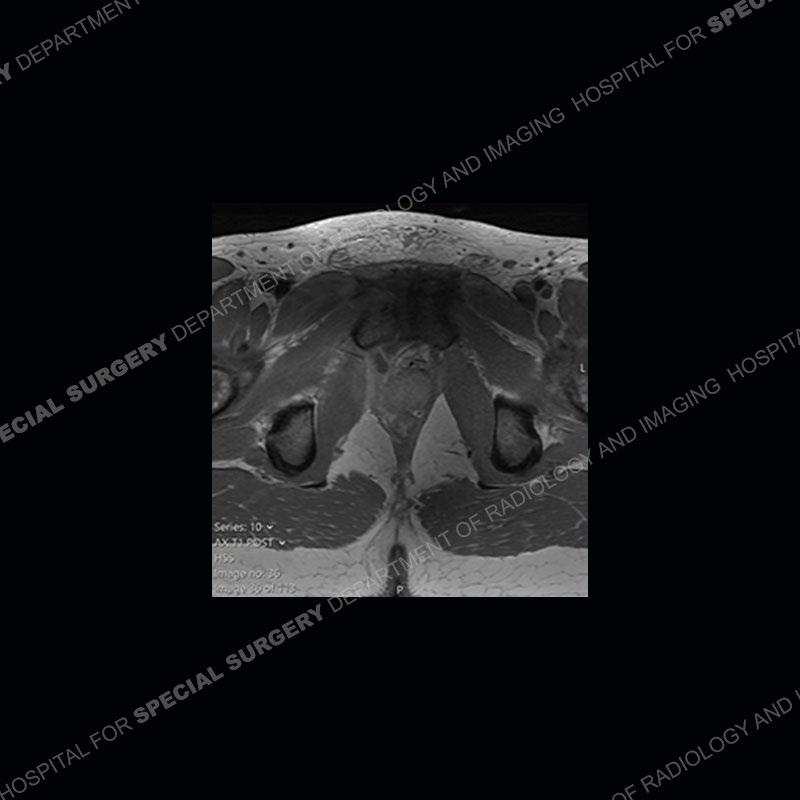

Radiographs did not demonstrate any clear abnormality. The MRI shows markedly abnormal signal of the right superior pubic ramus and abnormal signal/”mass” extending into the adjacent soft tissue. The inferior articular surface of the ramus showed what was thought to be bony destruction. CT examination shows a destructive process of the right superior pubic ramus.

Subsequent MRI in a very short time interval shows markedly increased abnormality of the ramus and increased edema and “mass” of the soft tissue. Post contrast imaging shows multiple, rim enhancing collections of the soft tissue and similar albeit less conspicuous enhancing collection of the ramus.